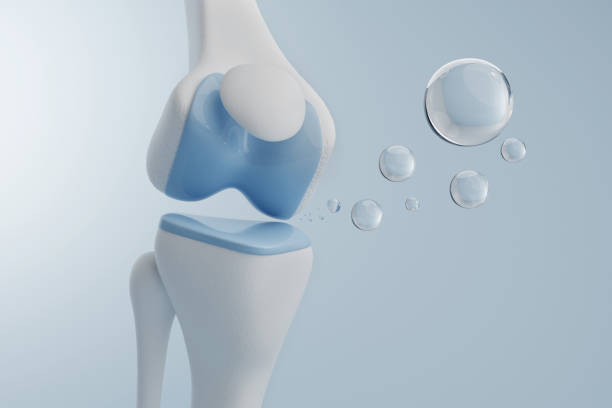

퇴행성 관절염은 나이가 들면서 관절의 연골이 닳아 없어지고, 관절 사이 간격이 좁아지며 뼈끼리 마찰이 생기는 질환입니다.

- 히알루론산 주사: 관절에 윤활 작용을 해주는 주사 치료, 보통 무릎에 주입

🔹 콘드로이틴 + 글루코사민 복합제

→ 관절 윤활 + 연골 보호